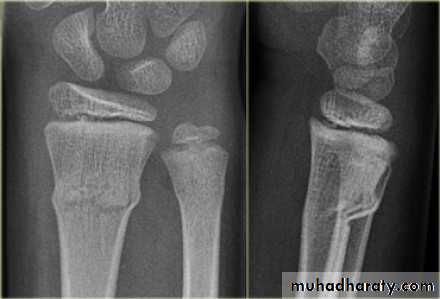

Fall on out stretched hand

xray